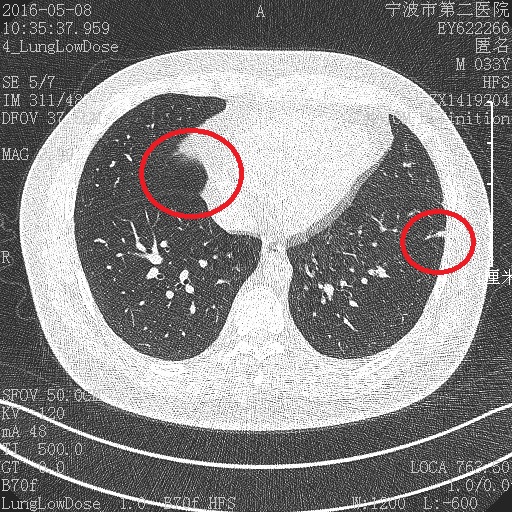

我前两天刚复查去年的肺部小结节,CT报告没变化,与去年相仿。我从医院拷回来的图片自己对比,发现一个问题,上面2张是2015年的,第三张是2016年的。2016复查的图层与2015年的不在一个图层上,不知为何?在线求解?同一医院,同一个CT机房(里面就1台机子,应该是同一台机器)

炎症